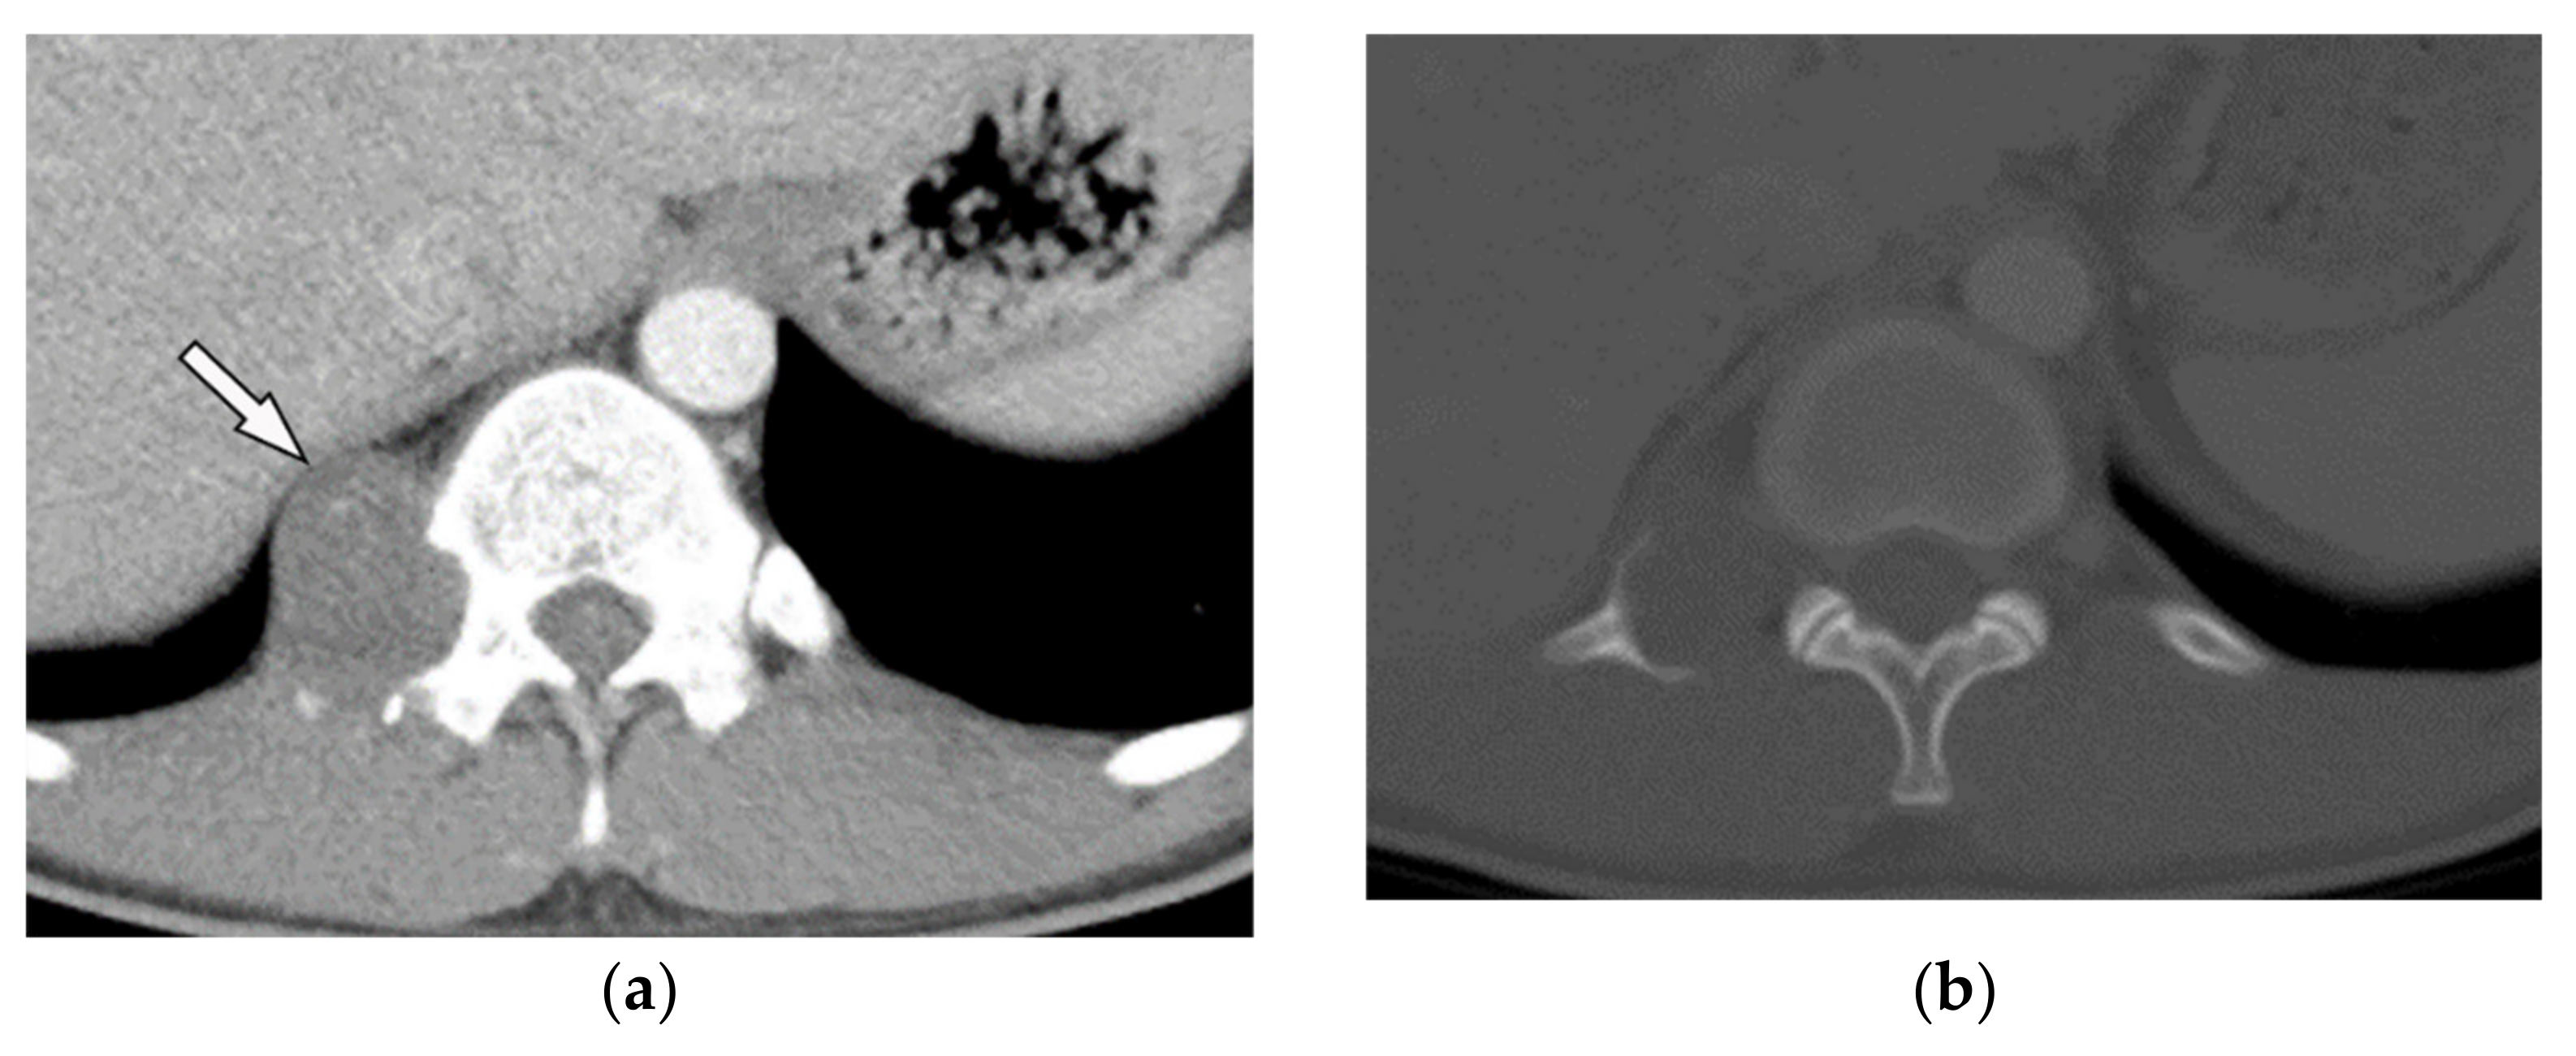

10.2. Liposarcoma

- Gaerte, S.C.; Meyer, C.A.; Winer-Muram, H.T.; Tarver, R.D.; Conces, D.J., Jr. Fat-containing lesions of the chest. Radiographics 2002, 22, S61–S78. [Google Scholar] [CrossRef]

- Baffour, F.I.; Wenger, D.E.; Broski, S.M. 18F-FDG PET/CT imaging features of lipomatous tumors. Am. J. Nucl. Med. Mol. Imaging 2020, 10, 74. [Google Scholar]

| Lipomatosis Tumors | ||

| Lipoma | Homogenous similar attenuation to macroscopic fat with approximate HU: −100. | T1W, T2W: signal intensity identical to subcutaneous fat T1WFS + C: no enhancement (mild enhancement can be visible for septa < 2 mm thickness) |

| Liposarcoma | A heterogeneous mass mixture of fat and soft tissue: higher attenuation than normal fat (hypercellularity), necrosis, and calcification in myxoid subtype. Attenuation similar to fat in well-differentiated subtype. Thick septa, enhancing solid component. | T1W: variable hyperintense (myxoid liposarcoma), hypointense (well-differentiated), and intermixed hyper and hypointense (dedifferentiated subtype) T2W: hyperintense (myxoid liposarcoma and dedifferentiated subtype) T1WFS + C: variable enhancement |